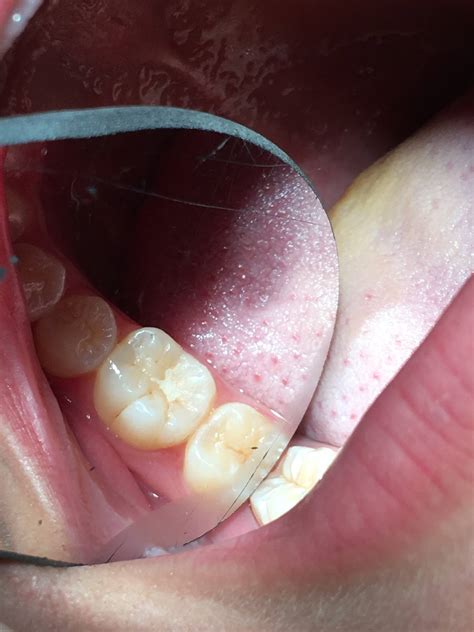

Researchers Are Finding Pit And Fissure Caries In Record Numbers

Pits And Fissure Caries Photos, Download The BEST Free Pits And Fissure